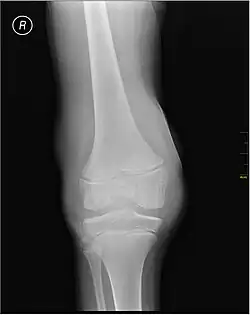

X-ray of Hemarthrosis

-